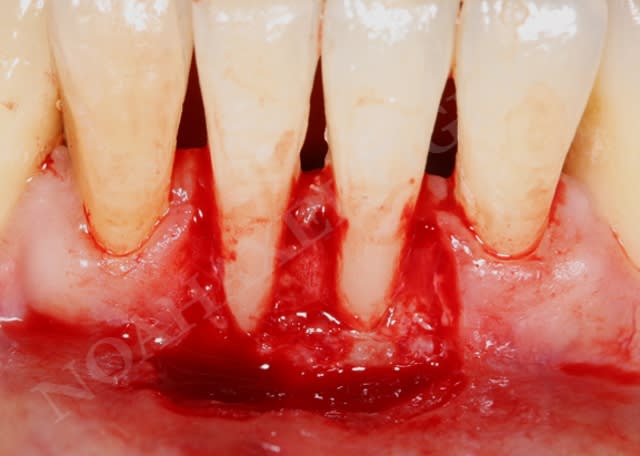

noahaxeltiger-olivier

13/02/2009 à 20h30

lors de la cicatrisation on remarque une amélioration gingivale au niveau de 32 et 42 mais malheureusement une récession persistante au niveau de 31 et surtout 41.

Lors de l'analyse des différents facteurs de cicatrisation, je note alors que 31 et surtout 41 sont mobiles grade 1 !!

Du coup, controle occlusal, contention et opération numero 2 (date de la semaine dernière) :